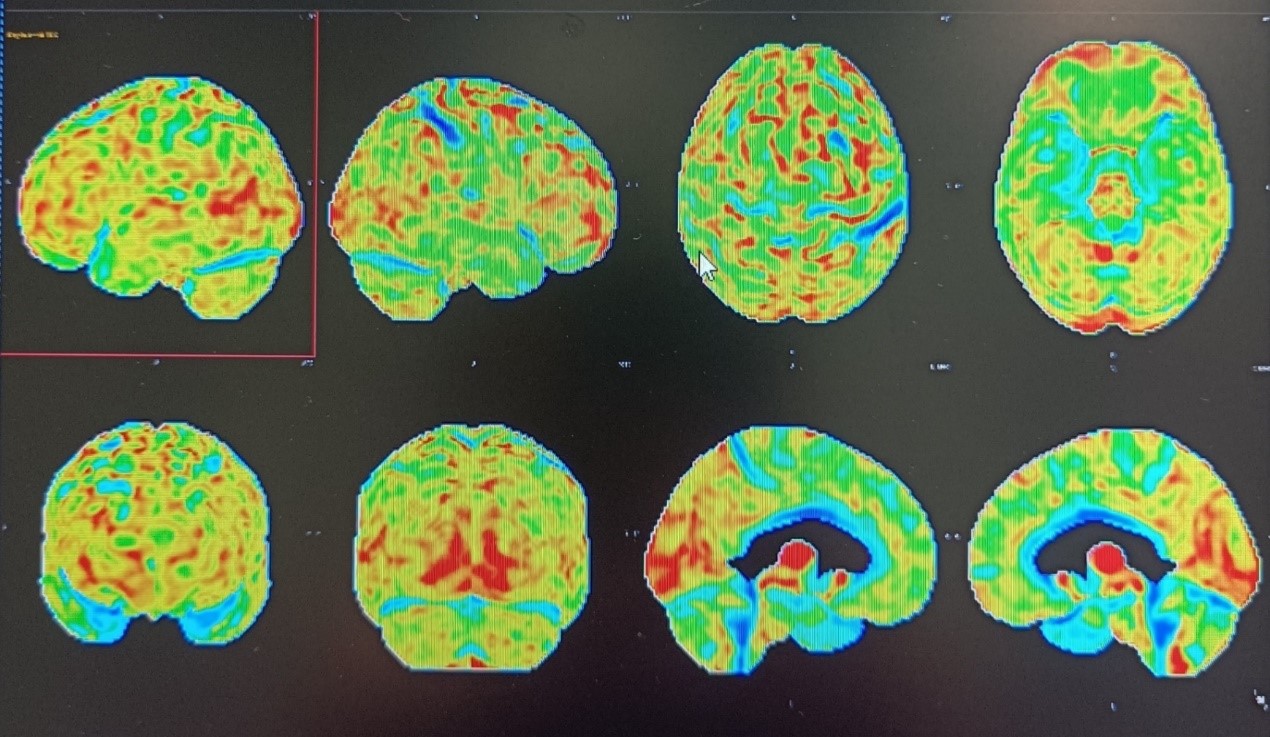

Amyloid PET imaging

It is an innovative, non-invasive, imaging technique for the early and accurate diagnosis of Alzheimer disease with extremely high sensitivity and specificity.

PET-CT DEPARTMENT, HYGEIA HOSPITAL